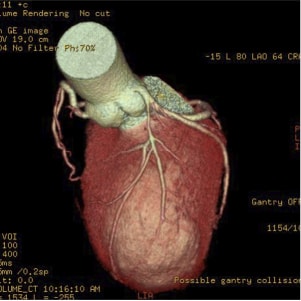

〈冠動脈CT〉

〈冠動脈CT〉冠動脈の閉塞の様子がわかります